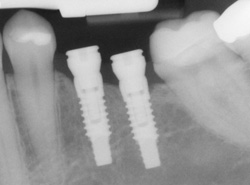

implants processAn implant is a new tooth made of materials that looks just like your natural tooth. Your implant is composed of two parts that mimic a tooth's root and crown. The implant's "root" is a titanium rod placed into the jaw bone to act as a root. Once the rod is in place, a porcelain crown is attached to replace the top part of your tooth.